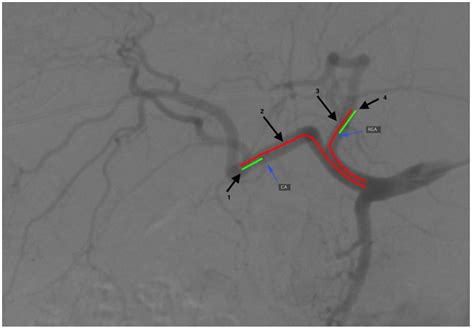

The origin of the Left Gastric Artery typically occurs at the celiac trunk, branching off alongside the splenic and common hepatic arteries. From its point of origin, the artery follows a distinct trajectory, ascending toward the esophageal hiatus of the diaphragm. During this initial phase, it often gives off esophageal branches that supply the distal esophagus, which later anastomose with branches from the thoracic aorta.

Upon reaching the cardiac region of the stomach, the artery makes a sharp turn, descending along the lesser curvature of the stomach between the two layers of the lesser omentum. Along this path, it provides vital blood supply to both the anterior and posterior surfaces of the stomach. Its final destination involves a significant anastomosis with the right gastric artery, creating a continuous vascular arch along the lesser curvature, which ensures collateral blood flow and structural integrity of the gastric walls.

While the standard anatomical textbook description places the Left Gastric Artery as a direct branch of the celiac trunk, anatomical variations are observed in a significant percentage of the population. These variations are particularly important for interventional radiologists performing hepatic or gastric embolizations.

💡 Note: Always perform a preoperative CT angiography or digital subtraction angiography when planning interventions involving the Left Gastric Artery to identify individual vascular mapping and prevent accidental damage to accessory vessels.